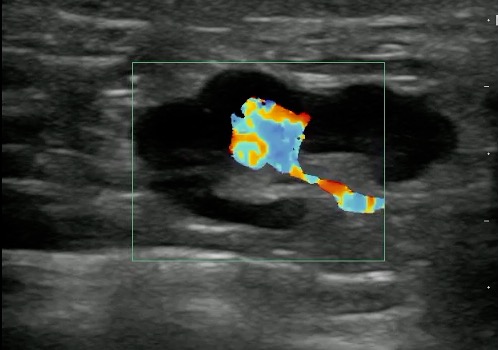

Video 9. Color doppler on lymph node

- Reactive lymphadenitis:

- Local infection or inflammation such as infections involving the pharynx, salivary glands, and scalp often cause reactive lymphadenitis.

- Normal reactive lymph nodes are enlarged, hypoechoic when compared with the surrounding structures. They still remain oval in shape.

- Vascularity is still confined to hilum of the lymph node and may be increased.

- Color Doppler of reactive lymphadenitis shows vascularity (normal along the hilum) which can differentiate from abscess cavity which has no flow within it.

Figure 13 and Video 10. Reactive lymph Node with increased Color Doppler